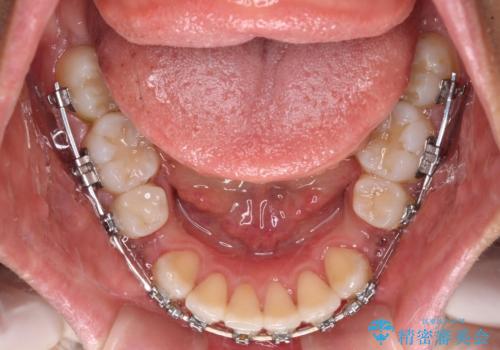

- 矯正装置

- メタルブラケット

- 出っ歯で唇が閉じにくいとのことで来院された患者様です。

顎先に力を入れないと唇が閉じきれない口元であったので、上下左右の第一小臼歯4本を抜歯して、ワイヤー装置にて矯正治療を行うこととしました。